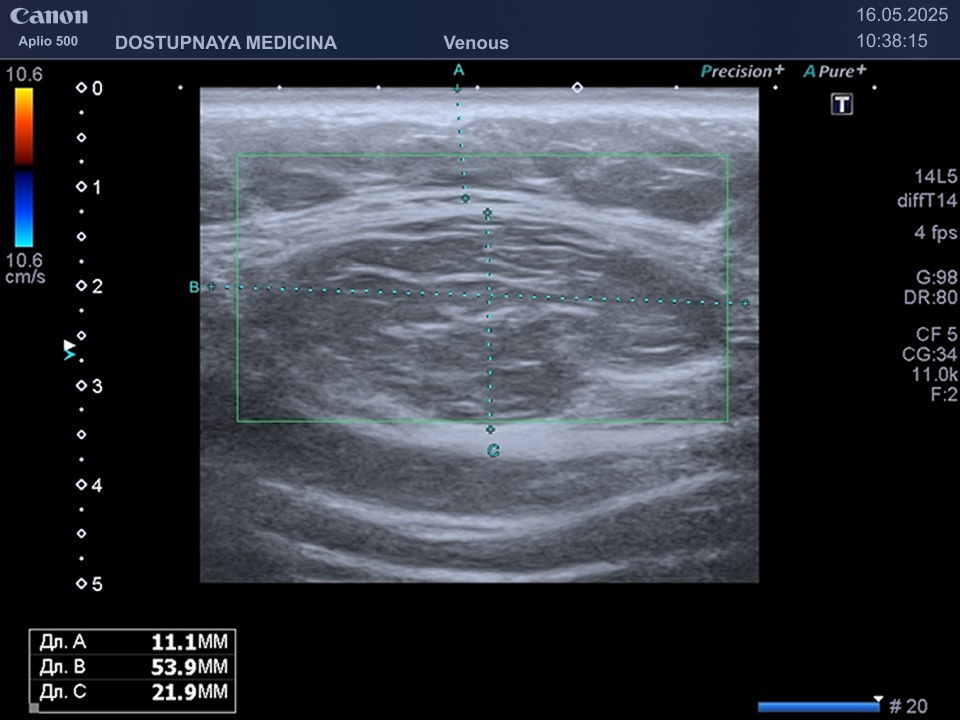

При ультразвуковом исследовании липома чаще всего выглядит, как гипоэхогенное образование овальной или округлой формы, мало отличающееся по своей эхоструктуре от окружающей её подкожной жировой клетчатки, без кровотока в режиме ЦДК. В описании заключения важно так же отметить прилежит ли близко опухоль к какому-либо кровеносному сосуду или нерву.